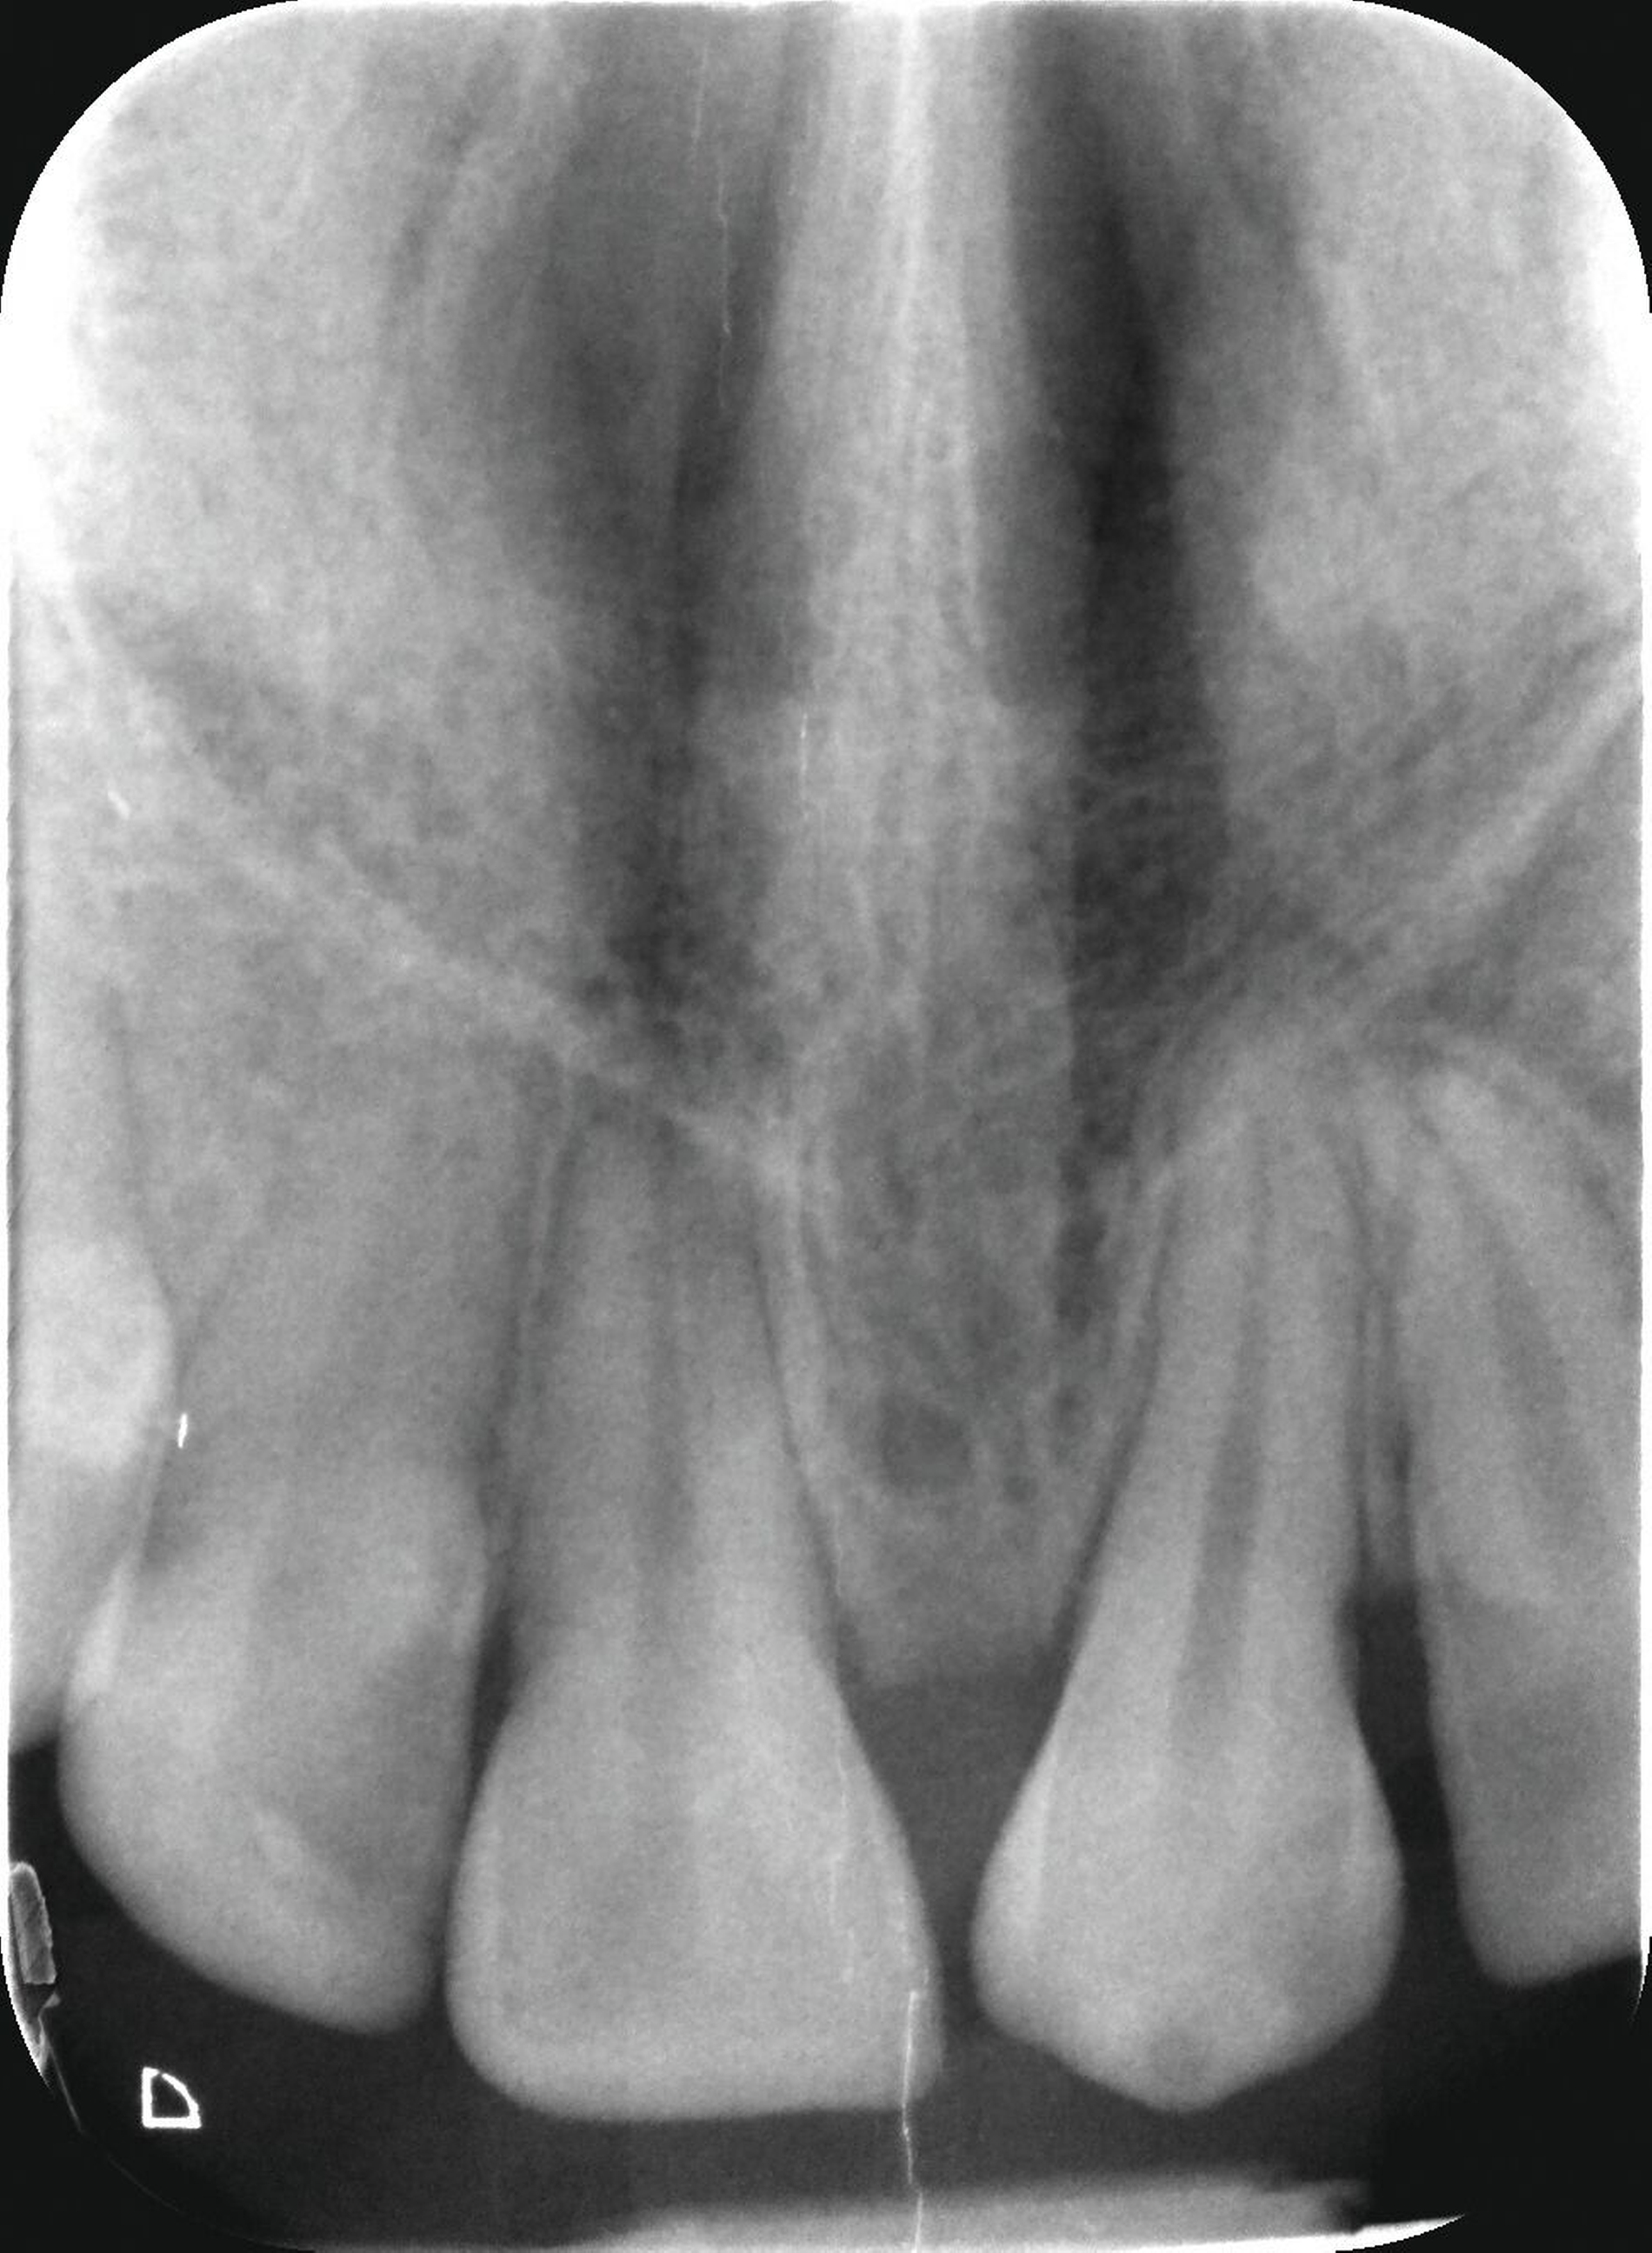

Die kieferorthopädische Behandlung der Patientin wurde im Mai 2018 (alio loco) begonnen. Zu diesem Zeitpunkt war die Patientin zehn Jahre alt. Bei der Erstellung des Behandlungsplans wurde der Fall initial als fehlender linker Eckzahn im Oberkiefer diagnostiziert. Vor der Extraktion des Schneidezahns wurde eine CT-Aufnahme durch den Erstbehandler angewiesen. Die Bildgebung ergab, dass der obere mittlere Schneidezahn sowie der Eckzahn auf der linken Seite betroffen waren (Abbildung 1). Die Patientin wurde daraufhin vom Erstbehandler zur Extraktion des impaktierten Zahnes 21 überwiesen.